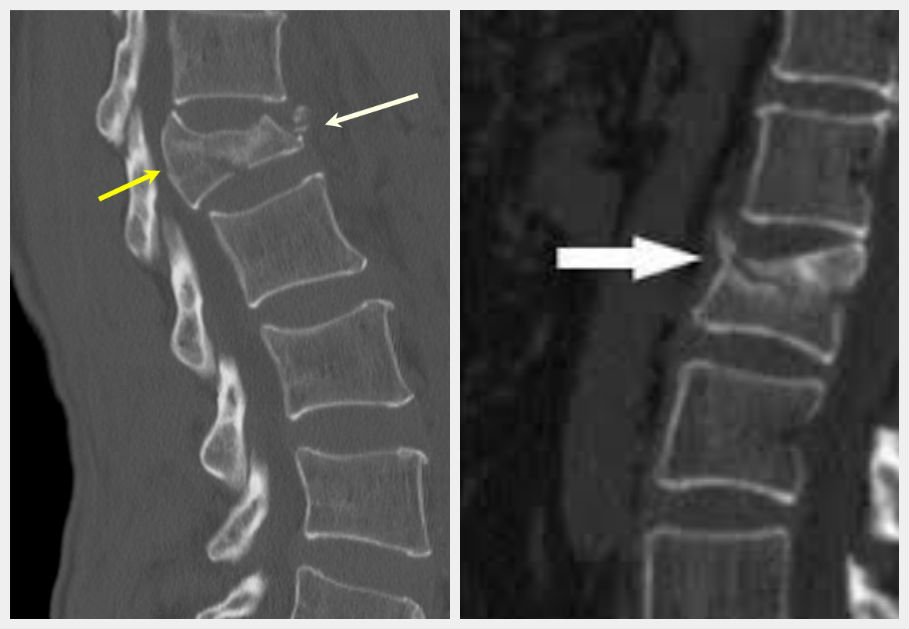

Диагностика

В медицинском учреждении врач-травматолог осматривает позвоночник пациента. Поврежденный участок определяется в области, где пациент испытывает сильную боль при прикосновении. Для подтверждения компрессионного перелома пациента направляют на рентгенографию. Снимки выполняются в прямой, боковой и промежуточной проекциях. Эта процедура позволяет выявить наличие осколков, патологии костной ткани и опухолевые образования. При переломе позвоночника могут быть назначены дополнительные обследования:

- компьютерная томография и магнитно-резонансная томография (МРТ);

Также пациенту могут назначить ректальное или вагинальное обследование для исключения наличия костных осколков. Обычно после рентгенографии становится ясна общая картина перелома, а дополнительные исследования проводятся для исключения патологий других систем организма.